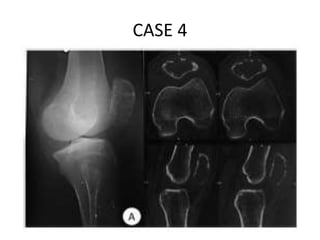

CASE 4